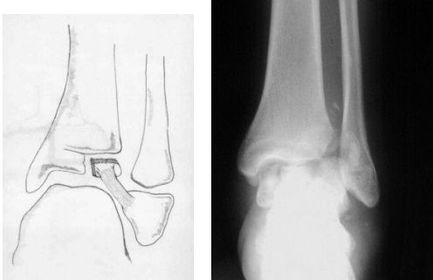

What type of fracture is this? How does it occur? | Tillaux fracture - a fracture of the anterolateral tibial epiphysis that is commonly seen in adolescents. The fragment is avulsed due to the strong ATF ligament in an external rotation injury of the foot. |